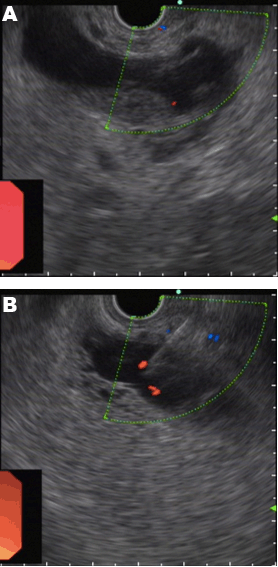

The patient was suspected of having malabsorption and a protein-losing enteropathy (PLE). Nevertheless first to elucidate whether the mass in pancreas was malignant or benign, the patient was subsequently referred to our center for an EUS evaluation. EUS was performed under deep sedation according to the principles of "monitored anesthesia care". The patient received oxygen, and blood pressure and heart rate were monitored during the procedure. The procedure was performed by a single experienced endosonographer with more than five years of EUS experience, who had performed more than 300 EUS procedures and more than 150 EUS–FNA annually. Curved linear-array EUS (GF-UCT 260; Olympus, Japan) was performed showing an anechoic cyst located at the head and neck of pancreas, approximately 2.3 cm in cross section. No perilesional lymphadenopathy was noted. The imaged portions of the liver, pancreas, and biliary tree were otherwise normal. A 22-gauge needle was advanced through the mucosa of duodenal wall and into the targeted lesion in pancreatic head (Figure 2) (EchoTip Ultra; Cook Endoscopy, Ireland). Fine-needle aspiration (FNA) was performed under EUS guidance whereas after three passes of drainage, yet no remarkable reduce of the size of cyst was observed. Approximately, 18 mL of chylous white fluid (Figure 3) was collected and sent for cytology and laboratory analysis.

Figure 2: (A) EUS view of the pancreatic cystic lesion. Radial scanning EUS image (5 mHz) showing cyst in pancreatic head. Color Doppler ultrasound was used to exclude interposed vessel in the needle path, (B) FNA was performed under EUS guidance after advancing needle through the mucosa of duodenal wall and into the targeted lesion in pancreatic head.